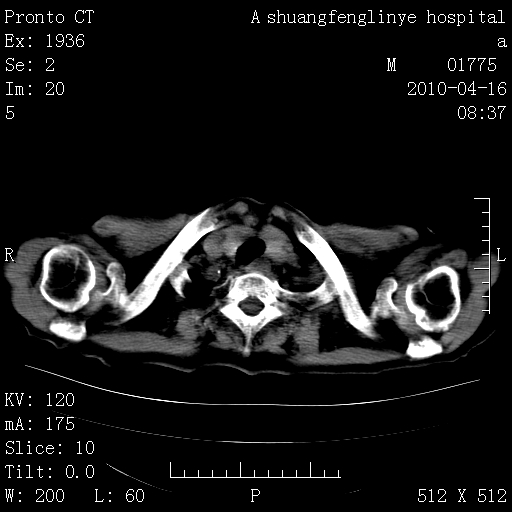

标题: CT25784:咳痰、请会诊!结核? [打印本页]

标题: CT25784:咳痰、请会诊!结核?

老年肺间质纤维化,肺动脉高压-----肺心病。

慢支肺气肿,左上陈旧性结核,主动脉冠脉钙化

1)左肺上叶结核(纤维、增殖病灶)。2)冠状动脉及主动脉钙化。

1)左肺上叶结核(纤维、增殖病灶)。2)冠状动脉及主动脉钙化。肺动脉高压